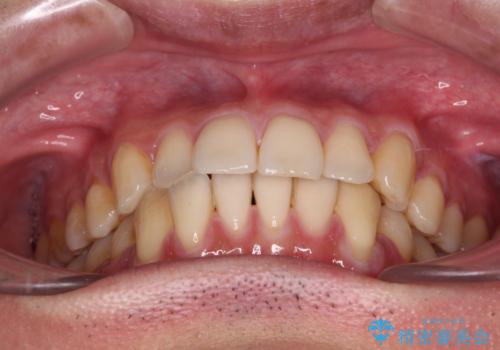

- 上下前歯のデコボコを気にして来院された患者様です。

口元の突出感や奥歯の咬み合わせに問題がなかったため、インビザラインの廉価版パッケージを用いるか上下ワイヤー装置での部分矯正を提案しました。

部分矯正は咬み合わせが不安定になったり、スペースができてしまったりと、適用となる患者様は極めて限られますが、こちらの方はスムーズに治療を終えることができました。